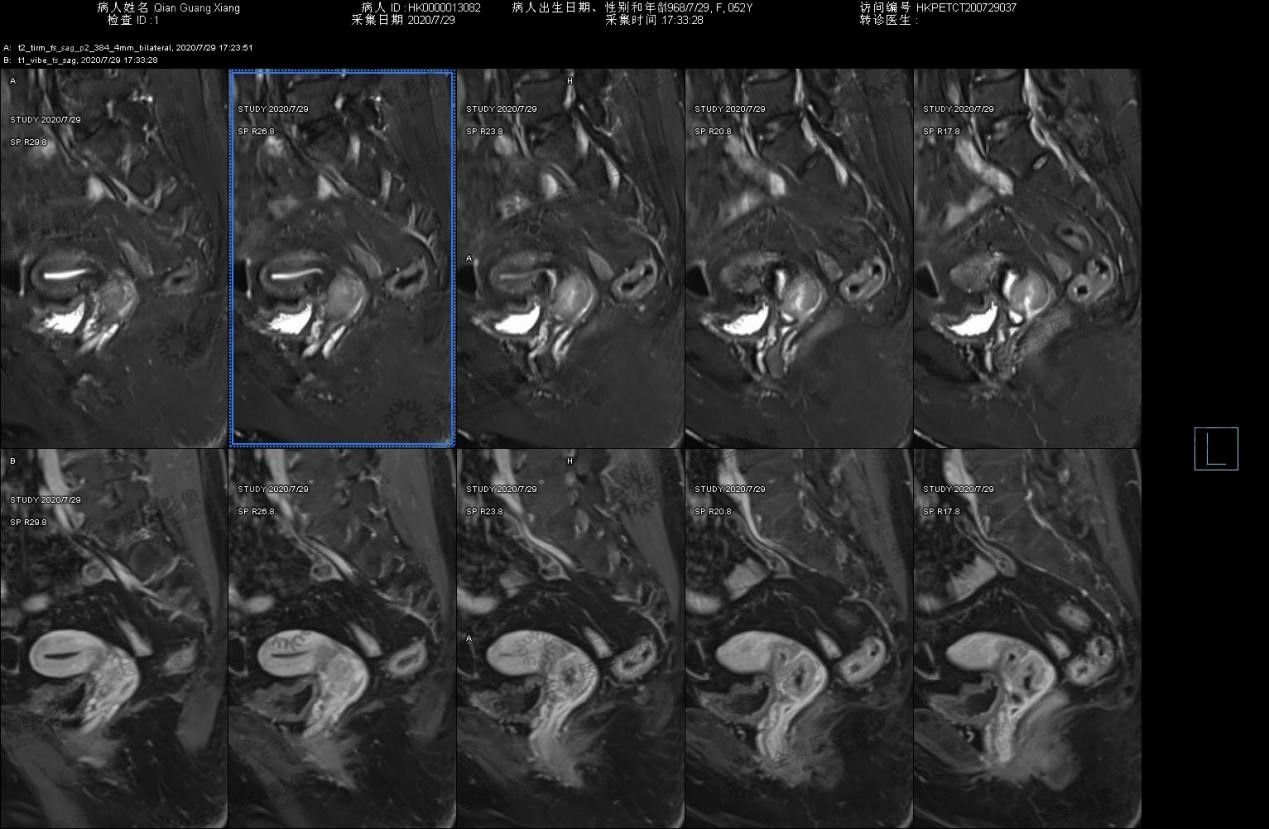

Abdominal MRI